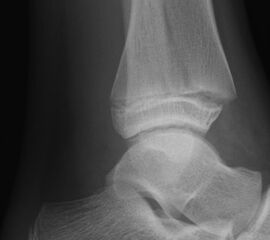

Fugengelenkfrakturen treten typischerweise vor dem 10. Lebensjahr auf, in einer Phase, in welcher die Wachstumsfugen noch weit offen sind. Dieser Frakturtyp betrifft fast ausschließlich den medialen Malleolus. Laterale Frakturen sind extrem selten, teilweise kommt es zu lateralen Bandverletzungen oder Fugenschaftfrakturen der distalen Fibula. Die Frakturlinie verläuft in einer Verlängerungslinie von der medialen Taluskante nach proximal. Häufig stellen sich Verletzungen des Innenknöchels im Röntgenbild schlechter dar, insbesondere wenn die Aufnahmen verdreht sind oder die Ebene der Fraktur bei geringer Dislokation verkippt zur Röntgenebene liegt. Besteht klinisch der geringste Hinweis auf eine Verletzung des Innenknöchels, muss aufgrund der Tragweite der Verletzung durch entsprechende Aufnahmen gegebenenfalls auch Schnittbildverfahren die Verletzung sicher diagnostiziert oder ausgeschlossen werden (Abb. 15).